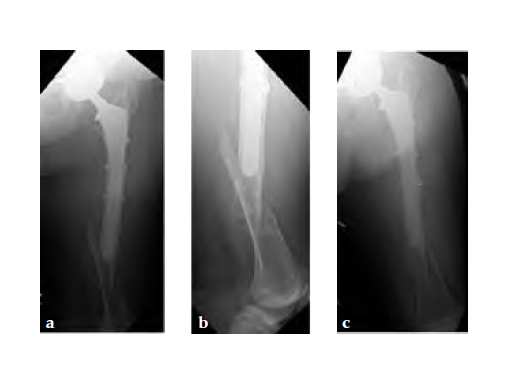

Case 2: A 76-year-old female with a Vancouver type C fracture.